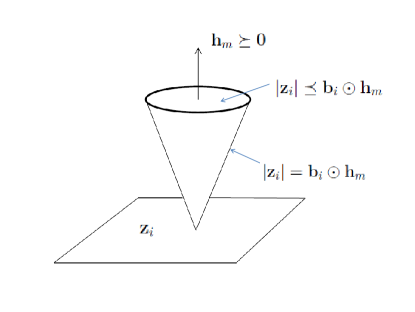

In each bilinear equation of the sensitivity encoded image functions, there are in general two independent variable vectors which, if known, can determine the third vector variable. Since the sensitivity functions have bounded magnitudes due to bounded inductances of the coils, there exist constant vectors such that , . It follows that the magnitudes of are constrained by

| (4) |

If and are considered as independent variables, for some , the inequality (4) forms a cone shaped convex hull, which contains the true solutions of and for the vector equation (3), if the constant bound vector is properly chosen. For the scalar case of and , such a convex solution space for and is displayed in Fig. 1, on top of the complex plane of . This convex solution space provides a basis for the convex optimization of the pMRI reconstruction problem and its extension to the high dimensional convex solution space is straightforward. It is, however, noted that the convex solution space only exists for the positive valued magnitude image but not for other real or complex valued image vectors.